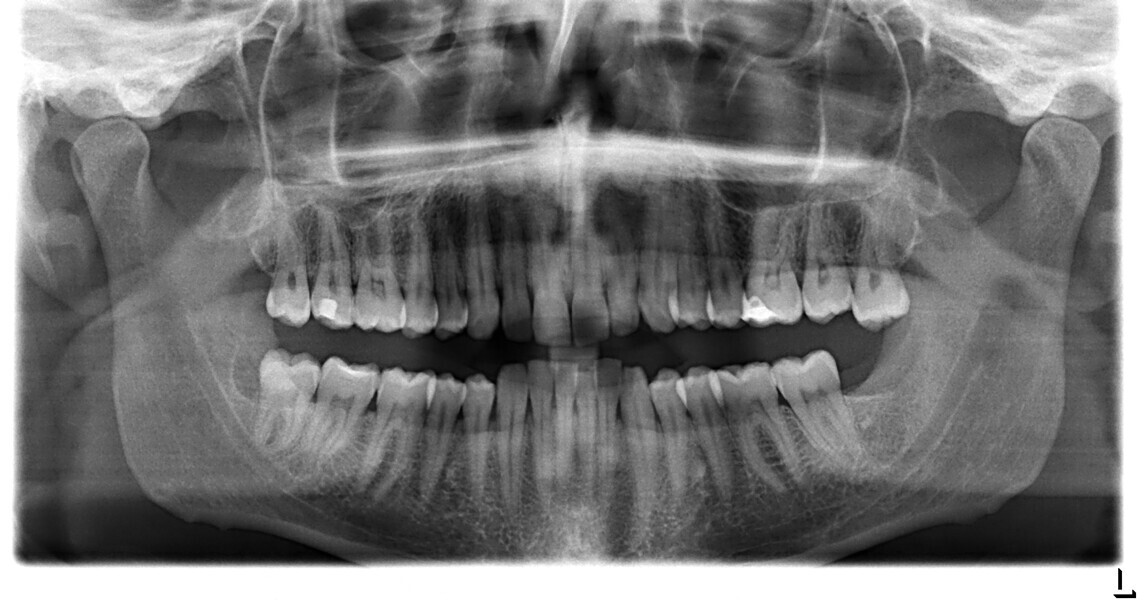

Le motif principal de consultation de ce patient âgé de 37 ans, était de rétablir l’alignement des dents antérieures sur les deux arcades. L’analyse faciale a indiqué une face courte avec un profil plat, mais une projection normale du menton (Figs. 9–12), et l’examen clinique a révélé une classe squelettique de type I (angle ANB = 0,89°) et une malocclusion de classe I avec supraclusion sévère (près de 100 %), une courbe de Spee très prononcée, un torque normal de l’incisive centrale supérieure (Ui-FH = 110°), un encombrement dentaire léger sur l’arcade maxillaire et modéré sur l’arcade mandibulaire (Figs. 13–18). Chez ce patient, les composantes de la supraclusion correspondaient à une dysmorphie squelettique grave correspondant à une hypodivergence (FMA = 14,24°), avec une inclinaison normale des incisives supérieures et inférieures et un angle goniaque réduit (110,46°). L’analyse du cliché céphalométrique indiquait une hauteur réduite de l’étage inférieur de la face associée à l’hypodivergence (Fig. 19). La seule option de traitement envisagée était un traitement orthodontique par aligneurs avec tous les éléments auxiliaires décrits (rampes d’occlusion, zones de pression, nivellement de la courbe de Spee dans les trois dimensions, élastiques de classe II et puissants contacts occlusaux) afin de corriger la supraclusion.

Le plan de traitement numérique (ClinCheck) avait prévu douze aligneurs pour l’arcade maxillaire et dix-sept pour l’arcade mandibulaire. Les objectifs du traitement visaient à combiner les mouvements verticaux d’extrusion des dents postérieures et les mouvements d’intrusion des dents antérieurs, au moyen de rampes d’occlusion, tout en utilisant des taquets d’extrusion pour assurer la désocclusion des dents postérieures et l’intrusion des dents antérieures inférieures, nécessaires au nivellement de l’arcade mandibulaire. La courbe de Spee a été nivelée et le profil plat ainsi que la position des lèvres ont été améliorés par une vestibulo-version des incisives supérieures et inférieures. Le plan avait prévu des élastiques de classe II pour faciliter la vestibulo-version des dents inférieures et les puissants contacts occlusaux postérieurs, avec une extrusion relative des dents postérieures. Une morphologie plus large de l’arcade et une intercuspidation idéale ont été obtenues par des mouvements de torque proches de 0° des dents latérales et postérieures supérieures. Aucune conception technique excessive n’avait été prévue dans le plan de traitement numérique. En raison de l’âge du patient, les aligneurs ont été changés tous les dix jours, dans le cadre d’un traitement d’une durée inférieure à six mois. À la fin de la première série d’aligneurs (Figs. 20–24), un nouveau plan de traitement numérique comportant cinq autres aligneurs a été conçu, en vue d’améliorer l’intercuspidation des molaires sans élastiques. La durée totale du traitement a donc été prolongée jusqu’à 7,5 mois puisque les aligneurs supplémentaires étaient changés toutes les semaines.

À la fin du traitement, on pouvait observer une relation de classe I des canines et des molaires, une légère augmentation de l’inclinaison des incisives supérieures (Ui-FH = 112°), une correction complète de l’inclinaison des incisives inférieures (IMPA = 97,09°) grâce à la vestibulo-version, et une légère amélioration de l’hypodivergence (SN-GoGn = 27°) résultant de l’extrusion relative des dents postérieures, et de l’utilisation d’élastiques de classe II — petite variation (1°) très intéressante compte tenu de l’âge du patient (Figs. 25–35). La ligne du sourire était harmonieuse et correspondait à une relation idéale entre les incisives supérieures et la lèvre inférieure. Le sourire avait été élargi grâce au contrôle du torque des segments latéraux et postérieurs.